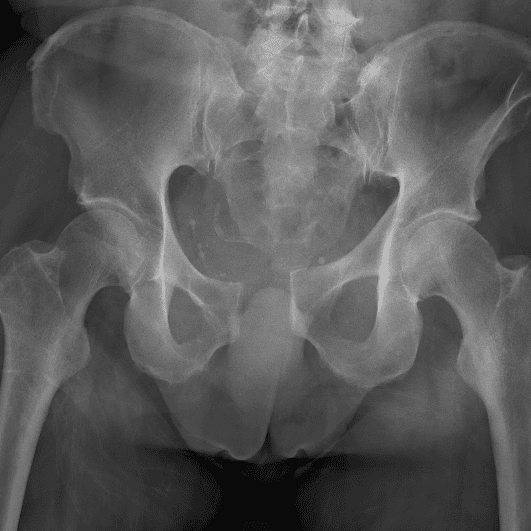

通过包含微妙或困难的病例和一些正常病例来模拟值班。

30 病例